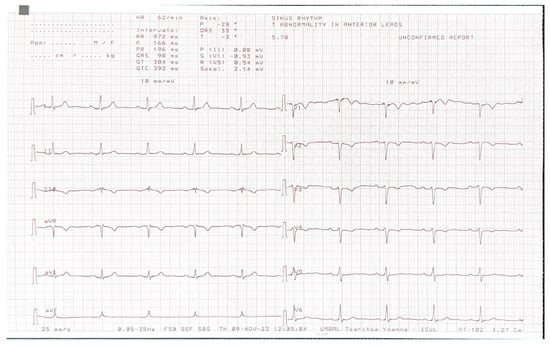

The CMR confirmed the abnormal position of the heart in the left hemithorax with laterally and posteriorly displaced apex and interposition of the lung tissue between the aorta and pulmonary trunk. There was no detectable pericardium overlying the left ventricular wall, and only a small discontinuous segments of pericardium were visualized surrounding the right atrium and right ventricular lateral wall (Figure 3 and Figure 4). Biventricular volumes and function were in the reference range. Additionally, a patent foramen ovale was visualized with no significant left-to-right shunt (Qp/Qs = 1.1).

Figure 3. (A)—Axial image of the chest shows the displacement of the heart into the left hemithorax with the cardiac apex pointing laterally and posteriorly. (B)—Coronal image of the chest demonstrates the interposition of lung tissue between the aorta and pulmonary artery (white arrow). Ao—aorta; PA—pulmonary artery.

In patients with CAP, the history and physical examination are often nonspecific and with no role in making the diagnosis. The ECG is usually normal in small or partial defects. In cases with complete pericardial absence, some typical findings include right axis deviation, complete or incomplete right bundle block and sinus bradycardia induced by vagal stimulation [7]. In these cases, chronic lung disease, congenital interventricular and interatrial septal defects with hemodynamically significant shunts should be considered. Echocardiography is also not characteristic, but some findings may raise the clinical suspicion of this diagnosis. They include unusual acoustic windows due to the abnormal heart position, right ventricle dilatation, cardiac hypermobility, “teardrop” appearance, and paradoxical motion of the interventricular septum [8]. In our case, a dilated right ventricle was registered at TTE, and in the presence of atrial septal defect (ASD), we referred the patient for CMR. Our differential diagnosis was for a significant left–right shunt. Chest X-ray finding in complete pericardial absence is known as “Snoopy sign” and include combination of levoposition of the heart, elongation and flattening of the left heart border, radiolucency between the pulmonary artery and aorta due to interposition of lung tissue and loss of the right heart border [7]. In the past, a diagnostic left pneumothorax has been used to confirm the diagnosis showing pneumopericardium [9]. Nowadays, the imaging modalities of choice for detecting pericardial absence are computed tomography and cardiac magnetic resonance. Since they are not affected by the acoustic window, they have a better sensitivity in identifying the levoposition of the heart and lung interposition in the aorto-pulmonary window and between the inferior cardiac border and the diaphragm. CMR is the gold standard for evaluating the cardiac anatomy, volumes and function and can demonstrate any functional abnormalities or regional bulging and herniation of the heart associated with pericardial agenesis. CT, on the other hand, has a greater spatial resolution and can be of help in identifying small defects [10,11].